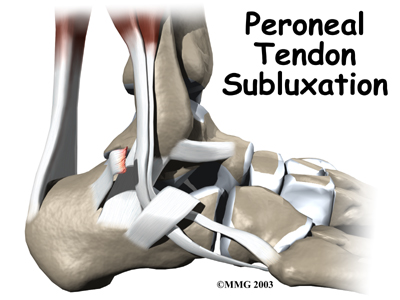

Welcome to Iron City Physical Therapy's patient resource about Peroneal Tendon Subluxation.

The peroneals are two muscles and their tendons that attach along the outer edge of the lower leg. The peroneal tendons are enclosed in a fibrous tunnel that runs behind the outside ankle bone (the lateral malleolus). Damage or injury to the structures that form and support this tunnel may lead to a condition in which the peroneal tendons snap out of place. This condition is called peroneal tendon subluxation.

The tendons of the peroneal muscles pass together through a groove behind the lateral malleolus. The tendons are kept within the groove by a sheath that forms a tunnel around the tendons. The surface of this sheath is reinforced by a band of ligament called a retinaculum. Contracting the peroneals makes the tendons glide in the groove like a pulley. This pulley action points the foot downward (plantarflexion) and outward (eversion).

The main cause of peroneal tendon subluxation is an ankle sprain. A sprain that injures the ligaments on the outer edge of the ankle can also damage the peroneal tendons. During the typical inversion ankle sprain, the foot rolls in. The forceful stretch on the peroneals can rip the retinaculum that keeps the peroneal tendons positioned in the groove. As a result, the tendons can jump out of the groove. The tendons usually relocate by snapping back into place.

Patients describe a popping or snapping sensation on the outer edge of the ankle. The tendons may even be seen to slip out of place along the lower tip of the fibula. It is common to feel pain and tenderness . There may also be swelling just behind the bottom edge of the fibula.